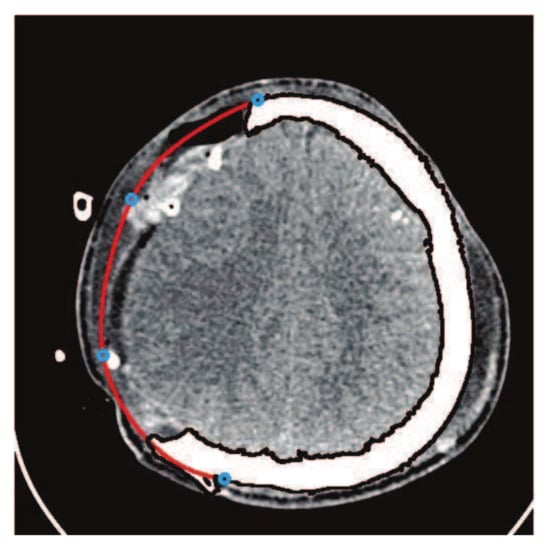

Figure 11. Construction of fractured part curve using C 1 rational Ball curves.

This subsection addresses the critical analysis of different schemes based on Bézier-like functions such as G C 2 , G C 1 , C 1 rational cubic Ball curves, NURBS curves and B-spline curve of degree three. Different types of fractures have been constructed using CT scan, such as in Figure 10. Initially, the C 1 rational cubic Ball curve is used to construct the boundary curve of the fractured part, as shown in Figure 11. This scheme works well for small fractures but it reduces the smoothness and flexibility when the defected part become bigger and irregular, as shown in Figure 12 and Figure 13. However, the results obtained by G C 1 , G C 2 rational cubic Ball curves are better, smoother and more flexible than the C 1 rational cubic Ball curve due to the presence of more shape parameters, as shown in Figure 14. The comparison of all curves is shown in Figure 15. In this figure, the red curve is obtained using the G C 1 rational Ball, the blue and green curves are obtained using the C 1 rational Ball.